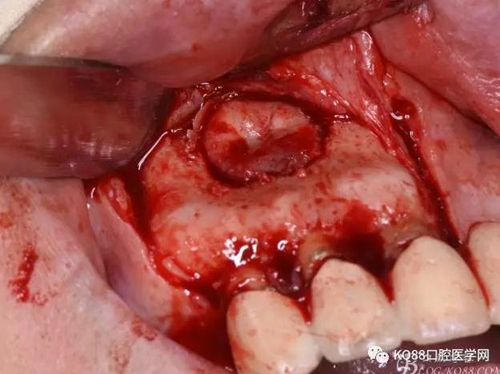

圖9.去除唇側(cè)薄的骨壁,暴露出囊壁

圖10.剝離囊壁